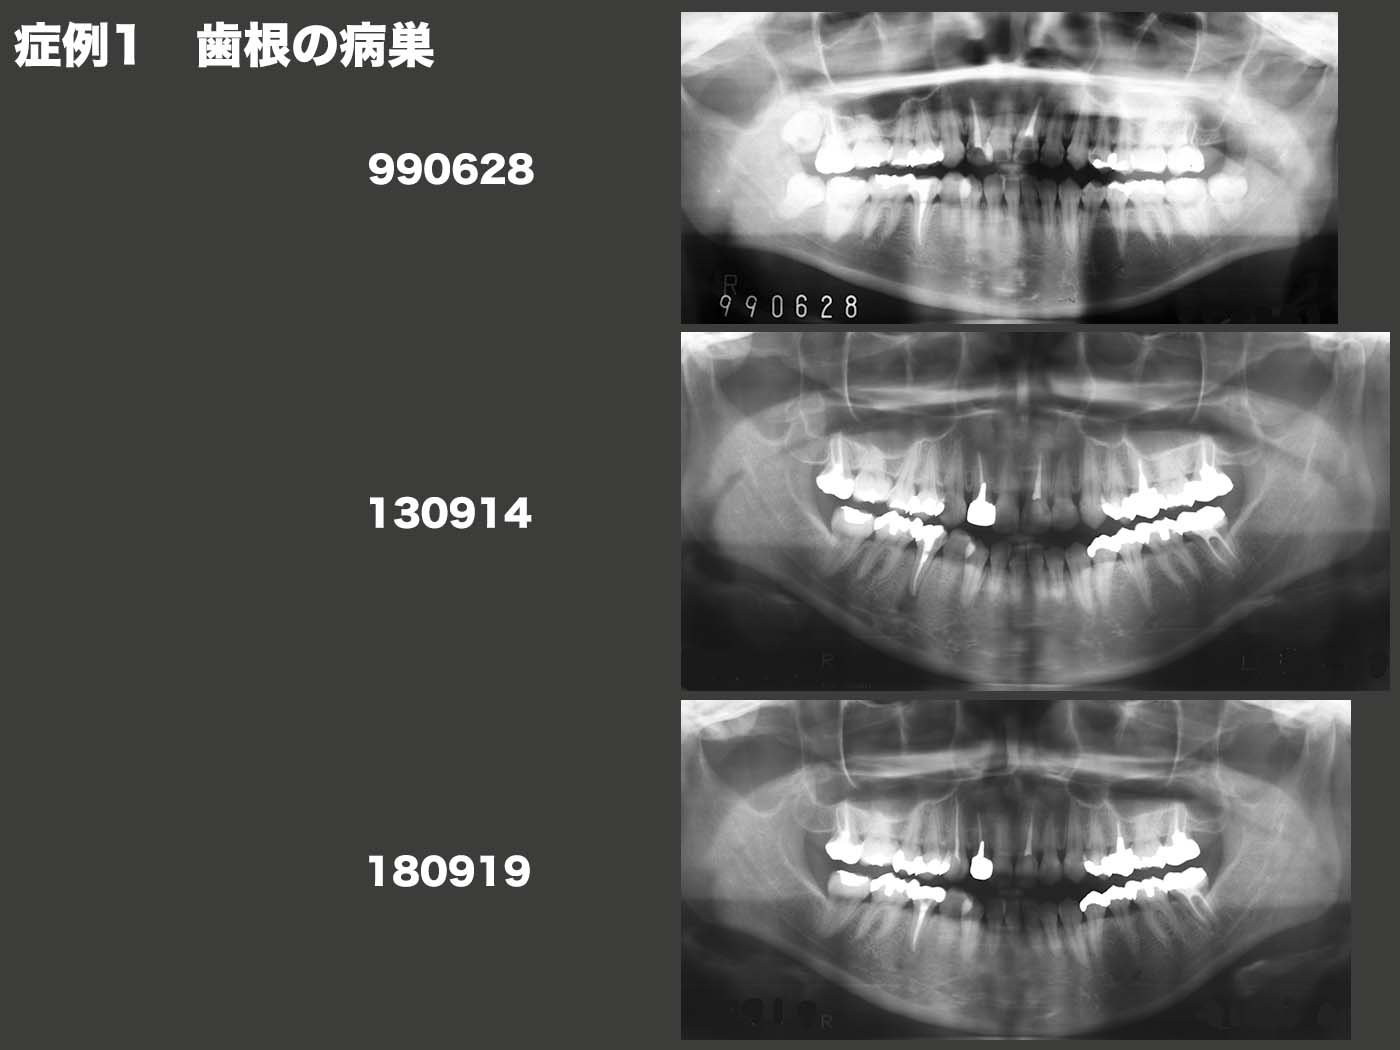

症例1 歯根の病巣

99年6月初診、22歳女性。パノラマX線写真より歯の中が黒く写っている虫歯が散見される。右下5は歯の中の神経が既にとられていた。13年9月、右上3の歯が痛いが主訴で来院した。ここでパノラマX線写真をとる と、右下5の根の先に黒く写っている病変が認められたため、歯の根の治療を施した。18年9月、左下7の歯ぐきが腫れたとのことで来院。この歯は、05年12月、虫歯が深く歯の痛みが強かったため当院で歯の神経をとった。しかし、治療が十分でなかったため、今回の症状に至ってしまった。この様に歯の神経をとって一見治ったようにみえても、暫くしてトラブルになることがある。やはり最初から歯の神経をとらないことが一番望まし い。なお、右下5の歯根の病変はほぼ治癒したと思われる。